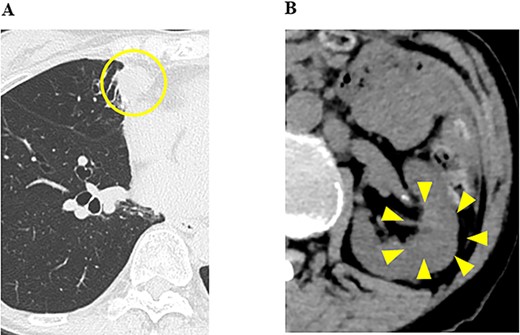

CT images of the chest and abdomen; (A) at the start of the administration of nivolumab and ipilimumab, CT showed multiple masses in both lung fields and a mass in the left kidney with a tumor plug in the left renal vein, and (B) 5 months after the administration of nivolumab and ipilimumab, CT showed increases in the sizes of the pulmonary tumors and a decrease in the size of the renal tumor, and (C) 6 months after the administration of nivolumab and ipilimumab, CT showed increases in the sizes of the pulmonary tumors and pleural effusion (yellow arrows).

In our hospital, CT-guided core needle biopsy was performed on the pulmonary mass of the right middle lobe. At the time of biopsy, which was performed ~1 month after the last CT scan, increases in the sizes of the pulmonary tumors (tumor growth rate of pulmonary tumors; 29%) (Fig. 1C-1) and pleural effusion (Fig. 1B-1) were noted on CT. A pathological examination revealed that the tumor formed a papillary structure and the lumen was filled with colloids. Since immunohistochemistry results were positive for Tg (Fig. 2), the mass was considered to be pulmonary metastasis of PTC. The patient was diagnosed with pulmonary metastases of PTC, and the administration of lenvatinib was initiated. Since nivolumab and ipilimumab were administered until just before the initiation of lenvatinib, the starting dose of lenvatinib was 8 mg/day. Fatigue (grade 2) and skin disorders (grade 2) developed 3 weeks after the initiation of lenvatinib, and thus, the dose was reduced to 4 mg/day. Three weeks after the dose reduction, hypertension (grade 2) was observed. The patient was administered olmesartan medoxomil, which returned blood pressure to normal.